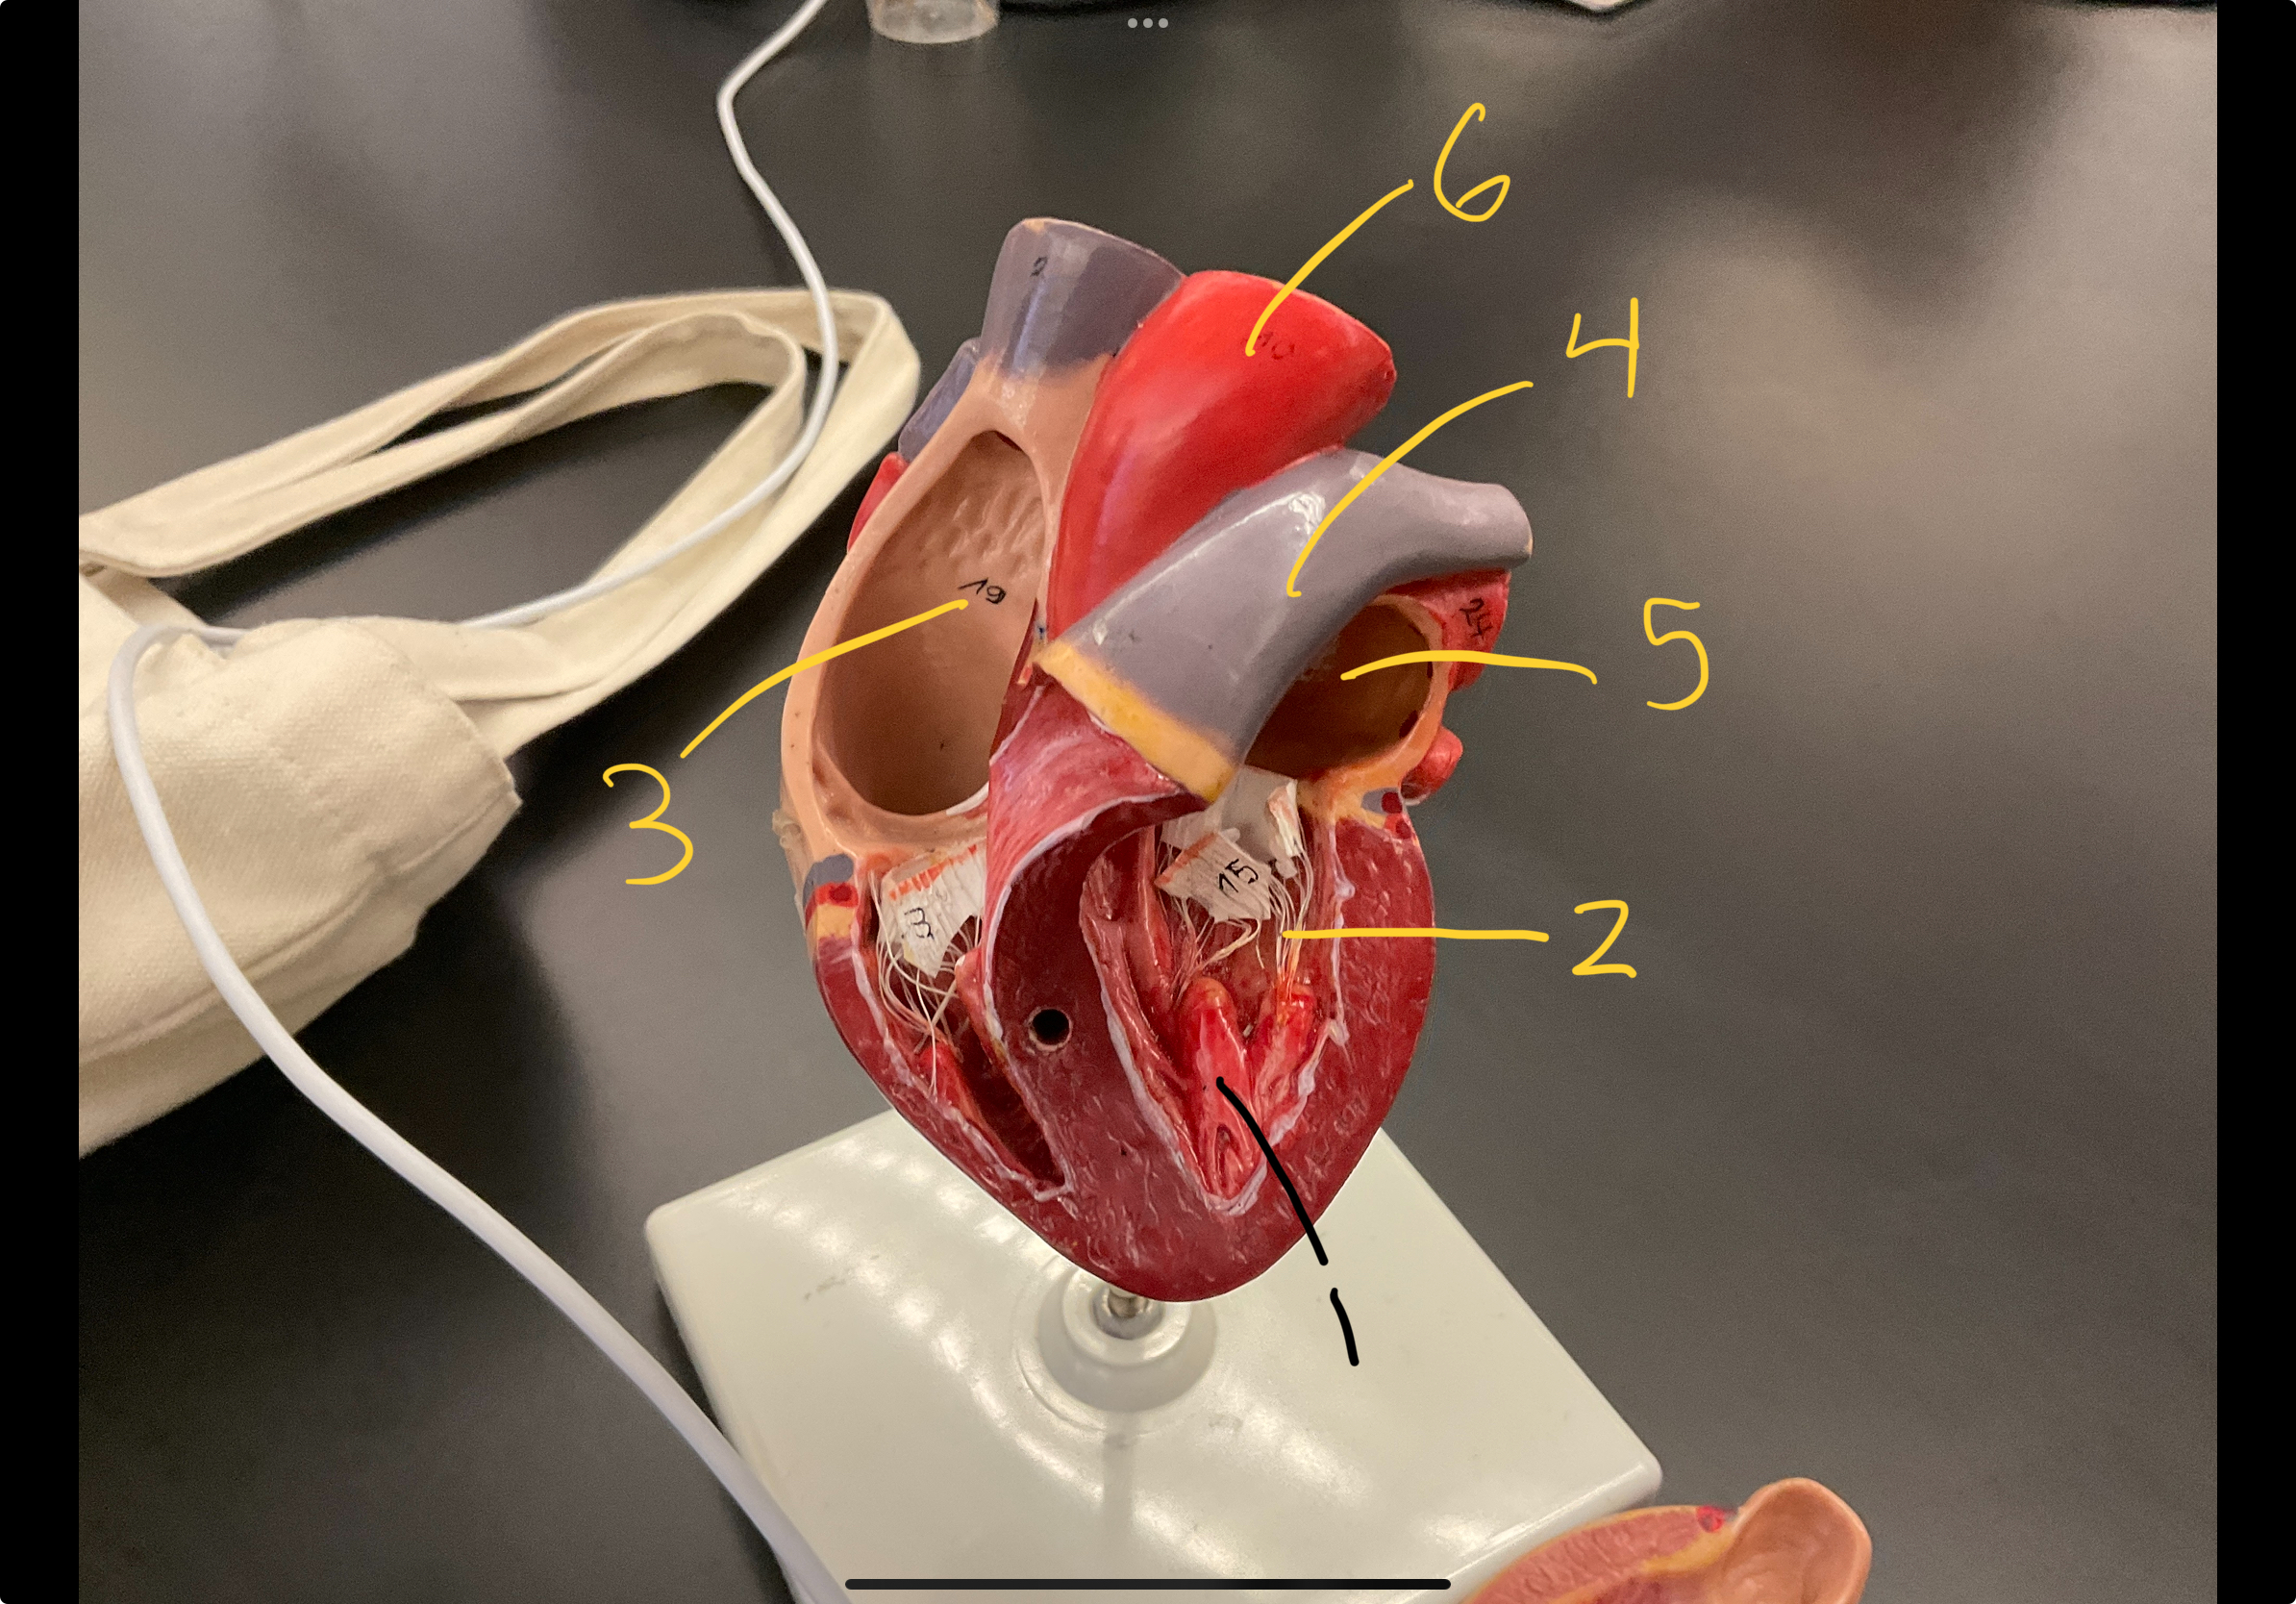

1

epicardium

2

3

endocardium

3

2

myocardium

4

1

coronary sinus

5

2

inferior vena cava

6

3

superior vena cava

7

1

right ventricle

8

2

left ventricle

9

3

bicuspid

10

4

tricuspid

11

5

interventricullar septum

12

6

left atrium

13

7

aorta

14

8

aortic trunk

15

9

pulmonary semi-lunar valve

18

1

papillary muscle

19

2

chordae tendineae